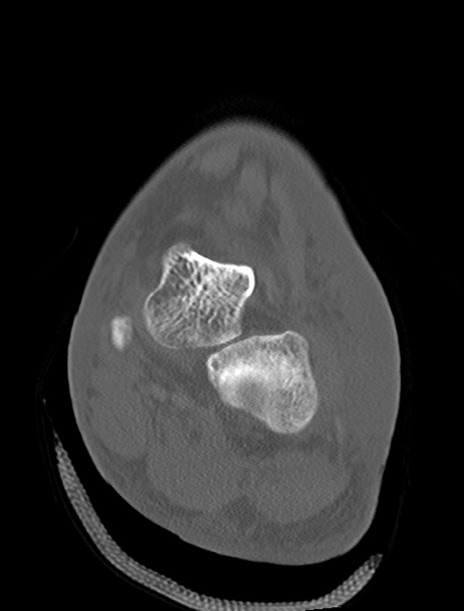

左足関節CT

横断像